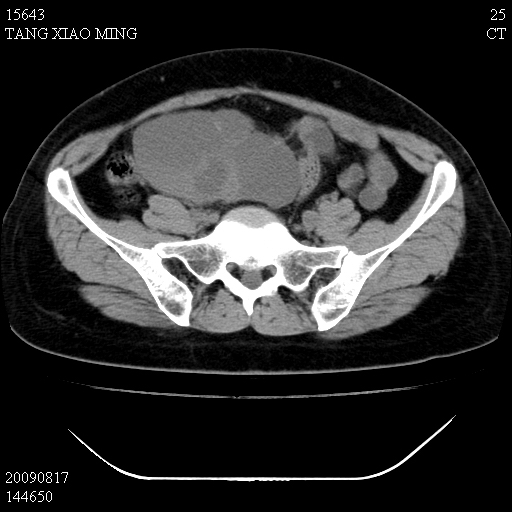

标题: CT21692:盆腔病变

女,33岁,右下腹痛2年余,既往宫外孕病史,如在我院手术,结果下周公布,

可能的诊断。1子宫内膜异位【子宫腺肌症并右卵巢巧克力囊肿】;2 右卵巢囊腺瘤。子宫肌瘤

1)考虑卵巢巧克力囊肿,不排除卵巢囊腺瘤。2)子宫肌瘤可能。

卵巢囊腺瘤,子宫肌瘤,直肠壁厚,不除外占位.